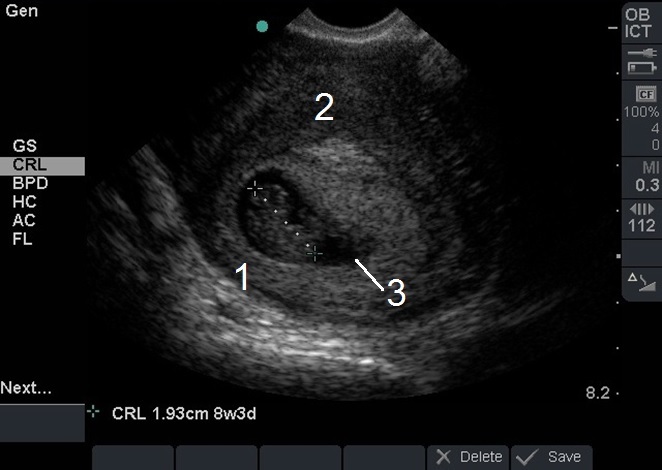

Pelvic Transvaginal (TV) Intrauterine Pregnancy (IUP) with Crown Rump Length (CRL) 8wk-3d Image

1. Fetal Pole

2. Uterus

3. Gestational Sac